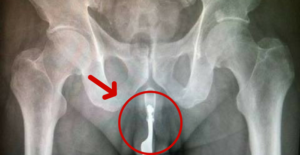

Arrivato al pronto soccorso ha detto "ho una forchetta nel pene aiutatemi" Non oso immaginare la faccia del medico di...